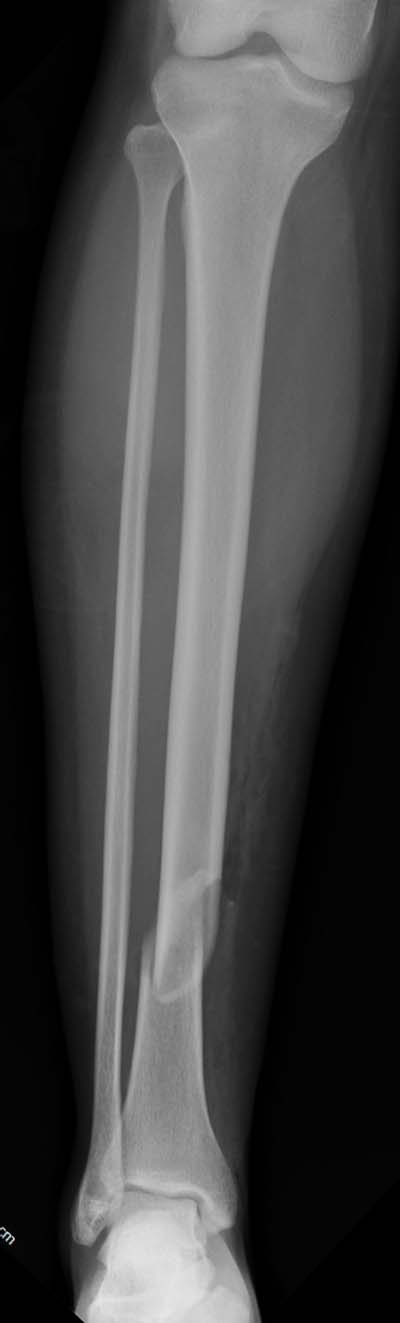

1. Гвоздь ОЧЕНЬ коротковат. Нет репозиции большеберецовой, гвоздь в дистальном отломке пошел по задней стенке.

2. Не зафиксирована малоберцовая кость: уровень перелома достаточно низкий, чтобы им пренебрегать. Да и состояние дистального синдесмоза сомнительное.

Хотя, по существу, гвоздь действительно короткий, и не смотря на это, заблокирован дистально только одним винтом - не стабильно

Не смотря на пойлерный винт остается варусное смещение дистального отломка и ротация его.

По моему, если бы вы выбрали гвоздь большего диаметра, многие проблемы бы решились

Разбор любого случая кому-то поможет лучше ориентироваться в решении вопросов, потому что в нашей работе встречаются разные связанные и несвязанные с мастерством хирурга ситуации. Возможно, отсутствие полного набора гвоздей повлияло на выбор короткого имплантата, имеется угловая и ротационная деформации. Независимо от локализации, стабильность создается, когда гвоздь проксимально не глубже 1.5 см (облегчает удаление) и дистально доходит до epiphyseal scar.

Мнение о том, что гвоздь сделает репозицию не всегда соответствует истине. Снимки показывают на неудачную попытку исправить направление гвоздя с помощью “поллеров”. Прием возможен только тогда, когда проход риминга в центре канала, иначе толкать гвоздь некуда.

Здесь несколько снимков изолированного перелома большеберцовой с интактной малоберцовой. Weber clamp, блокирующие спицы и риминг в центре канала отрепонировал перелом....